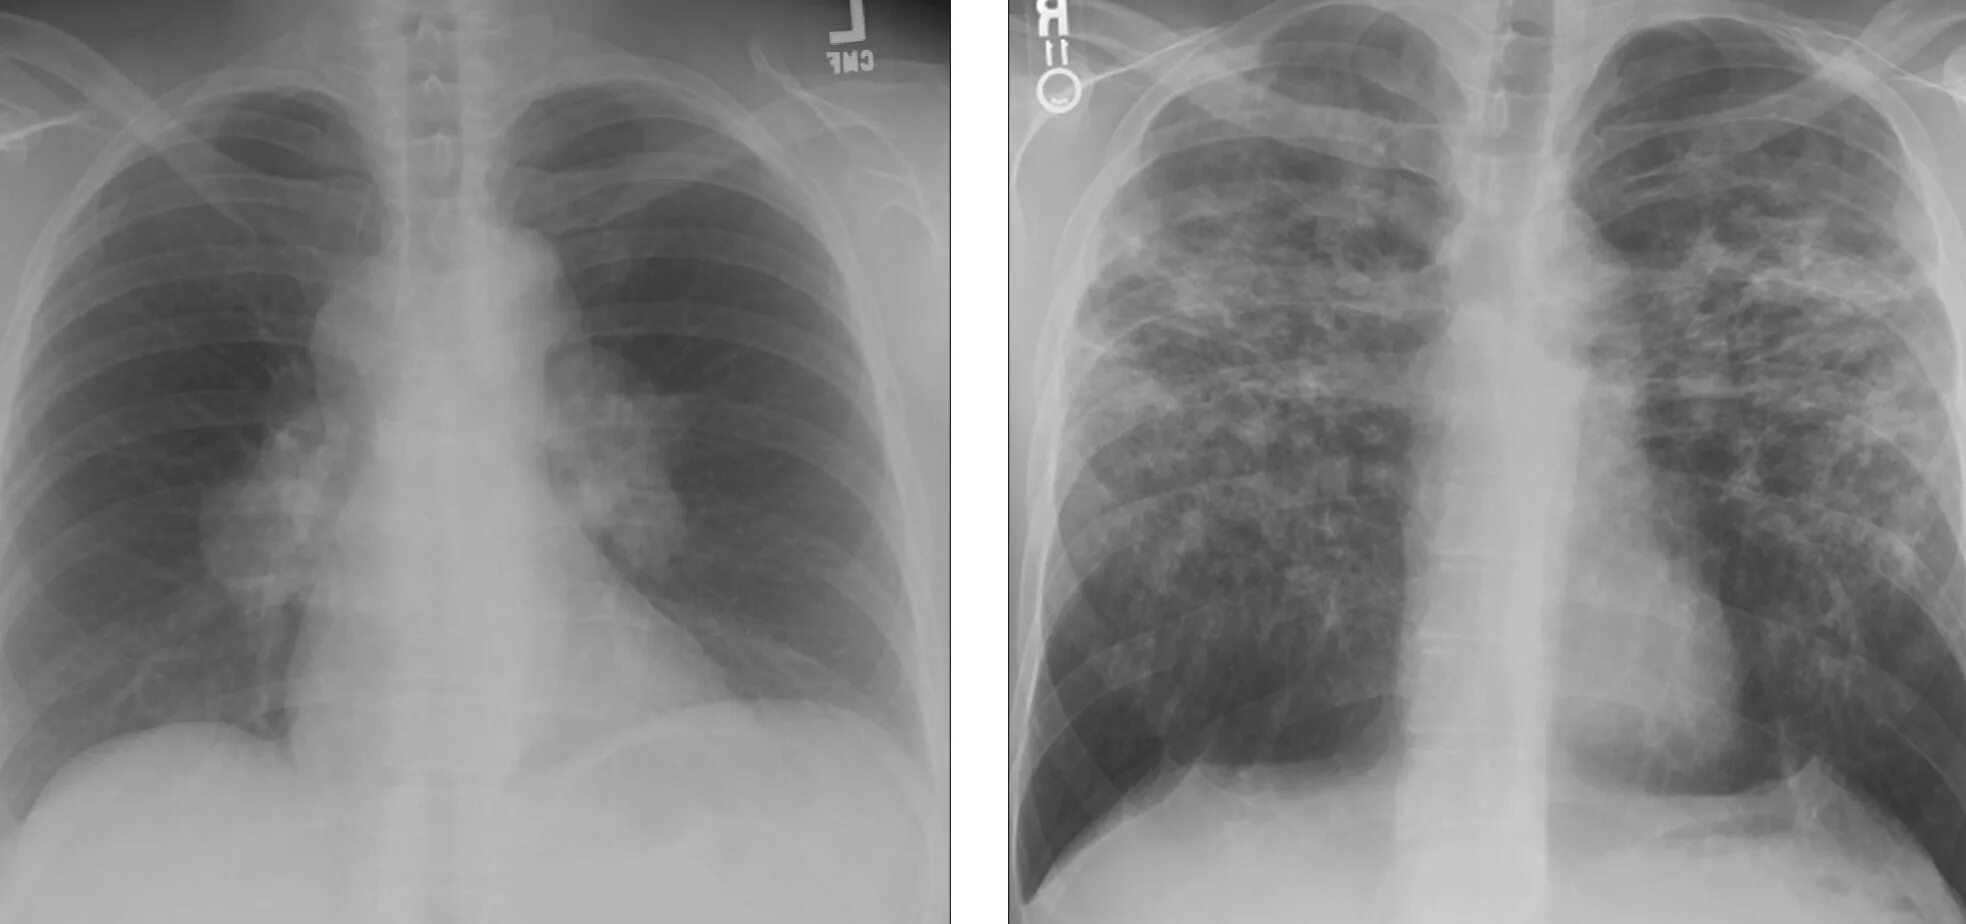

Саркоидоз 1